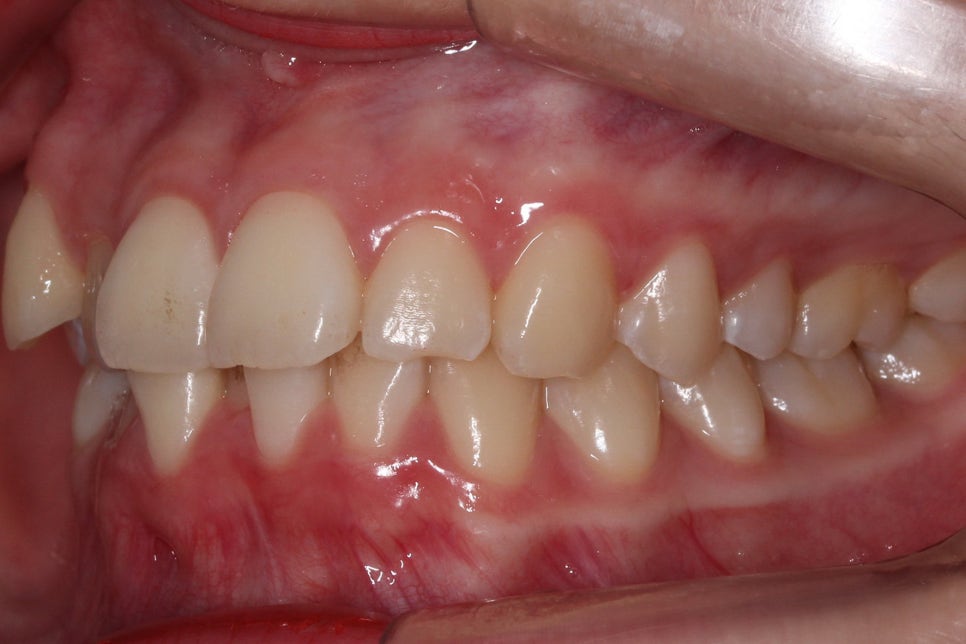

송곳니덧니 교정 Case로 구내사진을 보시면

사진 상으로 좌측 송곳니가 위쪽으로

변위되어 있는 모습을 확인할 수 있습니다.

이러한 송곳니덧니 증상은 복합적인

원인으로 발생하게 되는데요,

그 중 가장 영향이 큰 것은

영구치로 교체가 될 시기에

제 때 유치를 발치하지 않아

치아가 변위된 각도로 맹출되는 경우가 많습니다.

이러한 경우 쉽게 증상을 알아 보려면

치아가 맹출된 높이를 확인하는 것이 좋은데요,

사진처럼 송곳니가 맹출된 높이가

주변 치열보다 월등히 솟아 있는 경우

high canine라고 할 수 있으며

치아교정을 통해 올바른 위치로

조정할 수 있습니다.

다음으로 overbite 사진입니다.

전치부가 교합된 모습을 보면

상악에 비해 하악의 crowding이

심한 모습을 확인할 수 있는데요,

아랫니가 배열된 각도가 앞뒤로 심하게

삐뚤거리는 모습으로 이러한 경우

삐뚤어진 치아 사이 사이로

음식물이 쉽게 쌓이게 되고

치아를 관리하기가 어려워

치석이 발생할 수 있습니다.